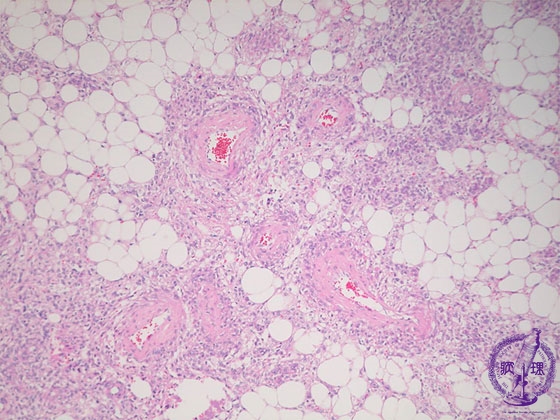

- (18)Angiomyolipoma(Tuberous sclerosis)

Microscopic findings ( HE, middle power view): The tumor contains adipose tissue, thick-walled blood vessels and smooth muscle-like spindle cells.